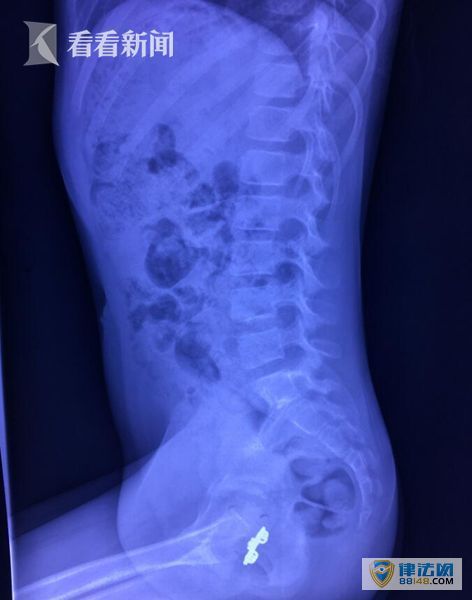

“正常孩子不可能会出现这样的情况,更何况这个情况从三年前才开始”泌尿科主任医师李爽表示“有理由怀疑这是异物没有及时发现引起的”。随即,在X光片检查下,医生的观点得到进一步证实,在孩子阴道部位清晰的可以看到一个镂空花纹的不规则长方体金属异物。医生当即安排楠楠住进了医院,第二天就安排了手术治疗,将“定居”阴道近3年的异物取了出来,一个1.4*2.5cm左右大小的金属发卡。